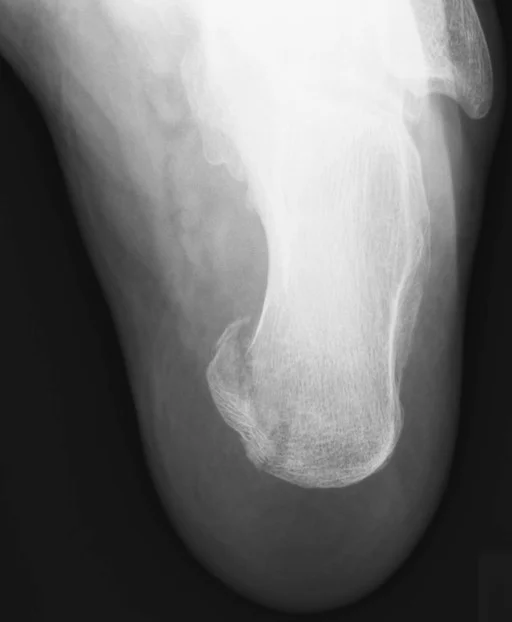

- Avulsion fracture

- Resisted muscle action, or where ligaments and tendons pull a bone fragment off

Avulsion Fractures

- Part of bone separated by forceful sudden resisted muscle action

- Caused by ligament or tendon pull on bone

- Part of bone avulsed – bone weaker than tendon/ligament